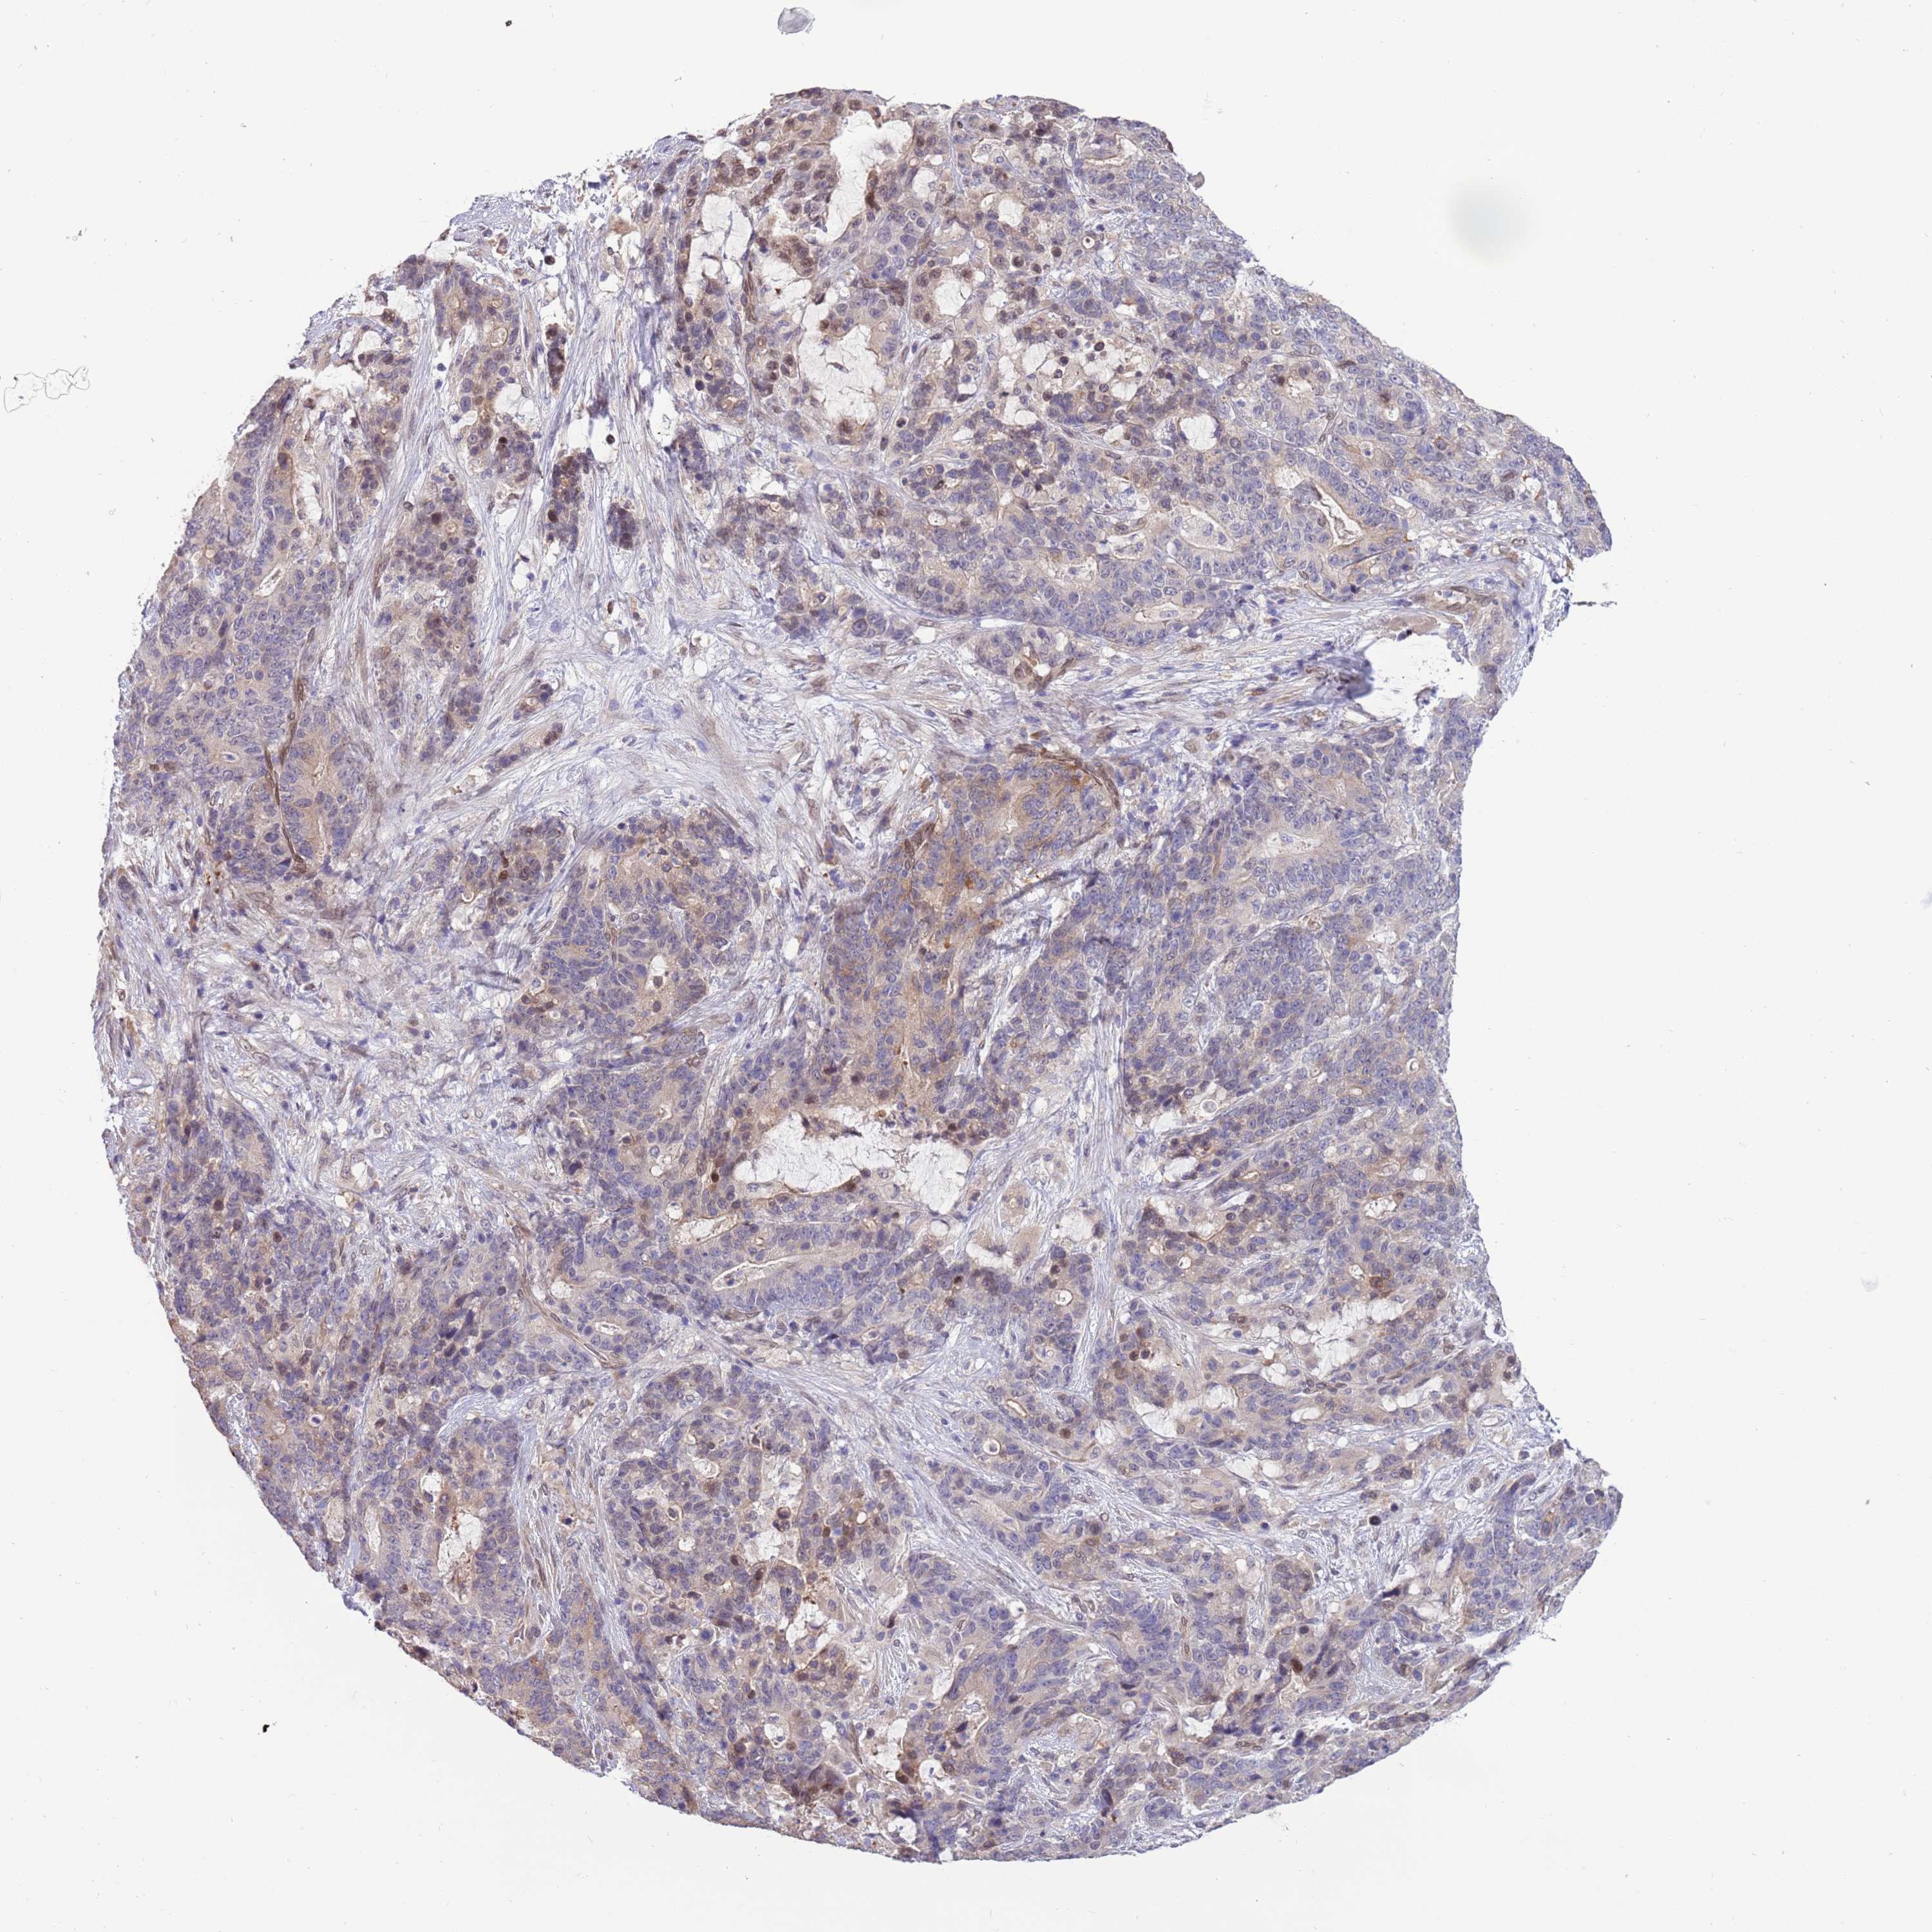

STOMACH CANCER - Protein expressioni

A mouse-over function shows sample information and annotation data. Click on an image to view it in a full screen mode. Samples can be filtered based on level of antibody staining by selecting one or several of the following categories: high, medium, low and not detected. The assay and annotation is described here.

Note that samples used for immunohistochemistry by the Human Protein Atlas do not correspond to samples in the TCGA dataset.

Antibody stainingi

Antibody staining in the annotated cell types in the current human tissue is reported as not detected, low, medium, or high, based on conventional immunohistochemistry profiling in selected tissues. This score is based on the combination of the staining intensity and fraction of stained cells.

Each image is clickable and will lead to virtual microscopy that enables deeper exploration of all samples and also displays staining intensity scores, fraction scores and subcellular localization as well as patient and tissue information for each sample.

Antibody HPA023437

Staining

High

Medium

Low

Not detected

Intensity

Strong

Moderate

Weak

Negative

Quantity

>75%

75%-25%

<25%

None

Location

Nuclear

Cytoplasmic/membranous

Cytoplasmic/membranous,nuclear

Adenocarcinoma, NOS